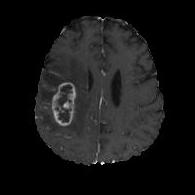

We argue that the sub-optimal paradigm of processing different abstractions within a single CNN pipeline can be remedied through the effective processing of information in a structured manner. Consequently, we devise strategies for disentangling the edge and texture information within a single training pipeline. Figure 2 illustrates how our proposed module, dubbed EG-CNN, can be paired with any existing CNN encoder-decoder to improve segmentation quality near intensity edges. We have applied our EG-CNN to the tasks of brain and liver tumor segmentation in medical images (Figure 3).

(1) Brain MR (2) Liver MR (3) Liver CT (4) Lung CT